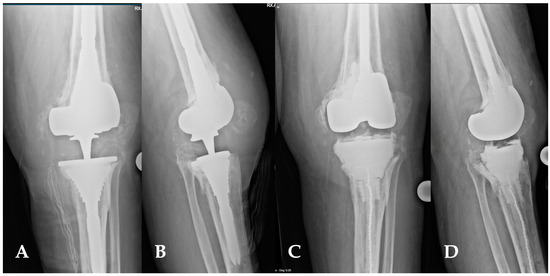

(A,D) This image depicts the comparison between preoperative and postoperative X-rays of a patient affected by periprosthetic joint infections of the knee (A,B). The patient’s characteristics met the inclusion criteria for the indication of a balanced articulating spacer. The spacer was constructed using cones and both asymmetrical and symmetrical augments, particularly to address the severe bone loss of the tibia (C,D).